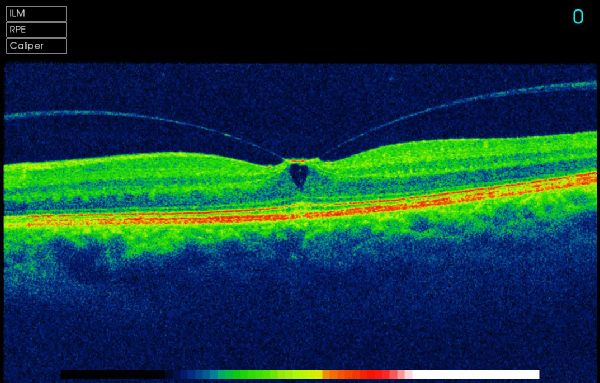

Optical Coherence Tomography uses low intensity infra-red light to give a 3D image of the back of the eye.  It shows not only the surface but also the depth of the structures.  It is similar to using ultrasound and creates an image not unlike an MRI or CT scan.

A 3D section of the layers ofthe retina and vitreous jellyA 3D section of the layers of the retina and vitreous jellyAge-related Macular Degeneration Dry FormAge-related Macular Degeneration Dry FormAge-related Macular Degeneration Wet FormAge-related Macular Degeneration Wet FormThe vitreous (jelly) pulling on the retinaThe vitreous (jelly) pulling on the retinaImage of Retina (back of the eye)Image of Retina (back of the eye)